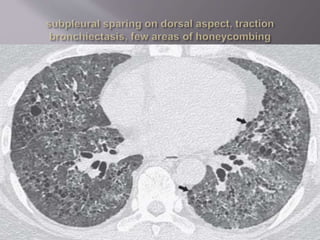

 Characteristic finding of NSIP is relative

sparing of the immediate subpleural lung in

dorsal region of lower lobe.

 Lower lobe predominance

 Traction bronchiectasis

 Subpleural sparing

 Extensive reticulation and

fibrosis